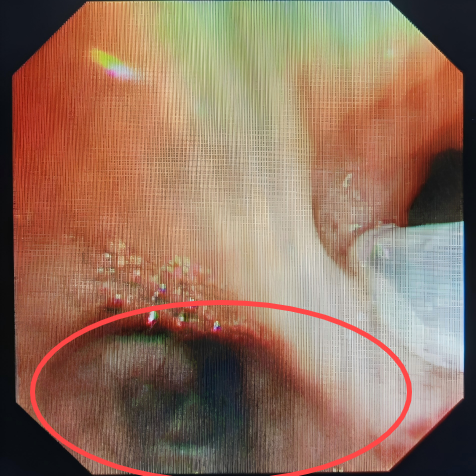

在实施支气管动脉栓塞术止血后,考虑到患者大量咯血后血液会阻塞气道,科室团队当即进行CT扫描,发现右肺已被凝血块完全阻塞,立即在床边通过气管镜清理气道内凝血块。术后,患者再无咯血,经住院治疗一段时间后,患者复查CT右肺基本恢复,顺利出院。

床边支气管镜清理凝血块

患者郑某某,因支气管扩张、空洞反复咯血十余年,再次复发后,咯血量明显增多,在当地治疗一周因效果不佳转入我院,就诊于急诊时仍咯血200ml,呼吸与危重症医学科立即启动绿色通道将患者送入介入室手术,术中仍持续咯血,在实施支气管动脉栓塞术后,患者咯血立即停止。在呼吸与危重症医学科医护人员的精心治疗下,患者最终好转出院,至今无复发。